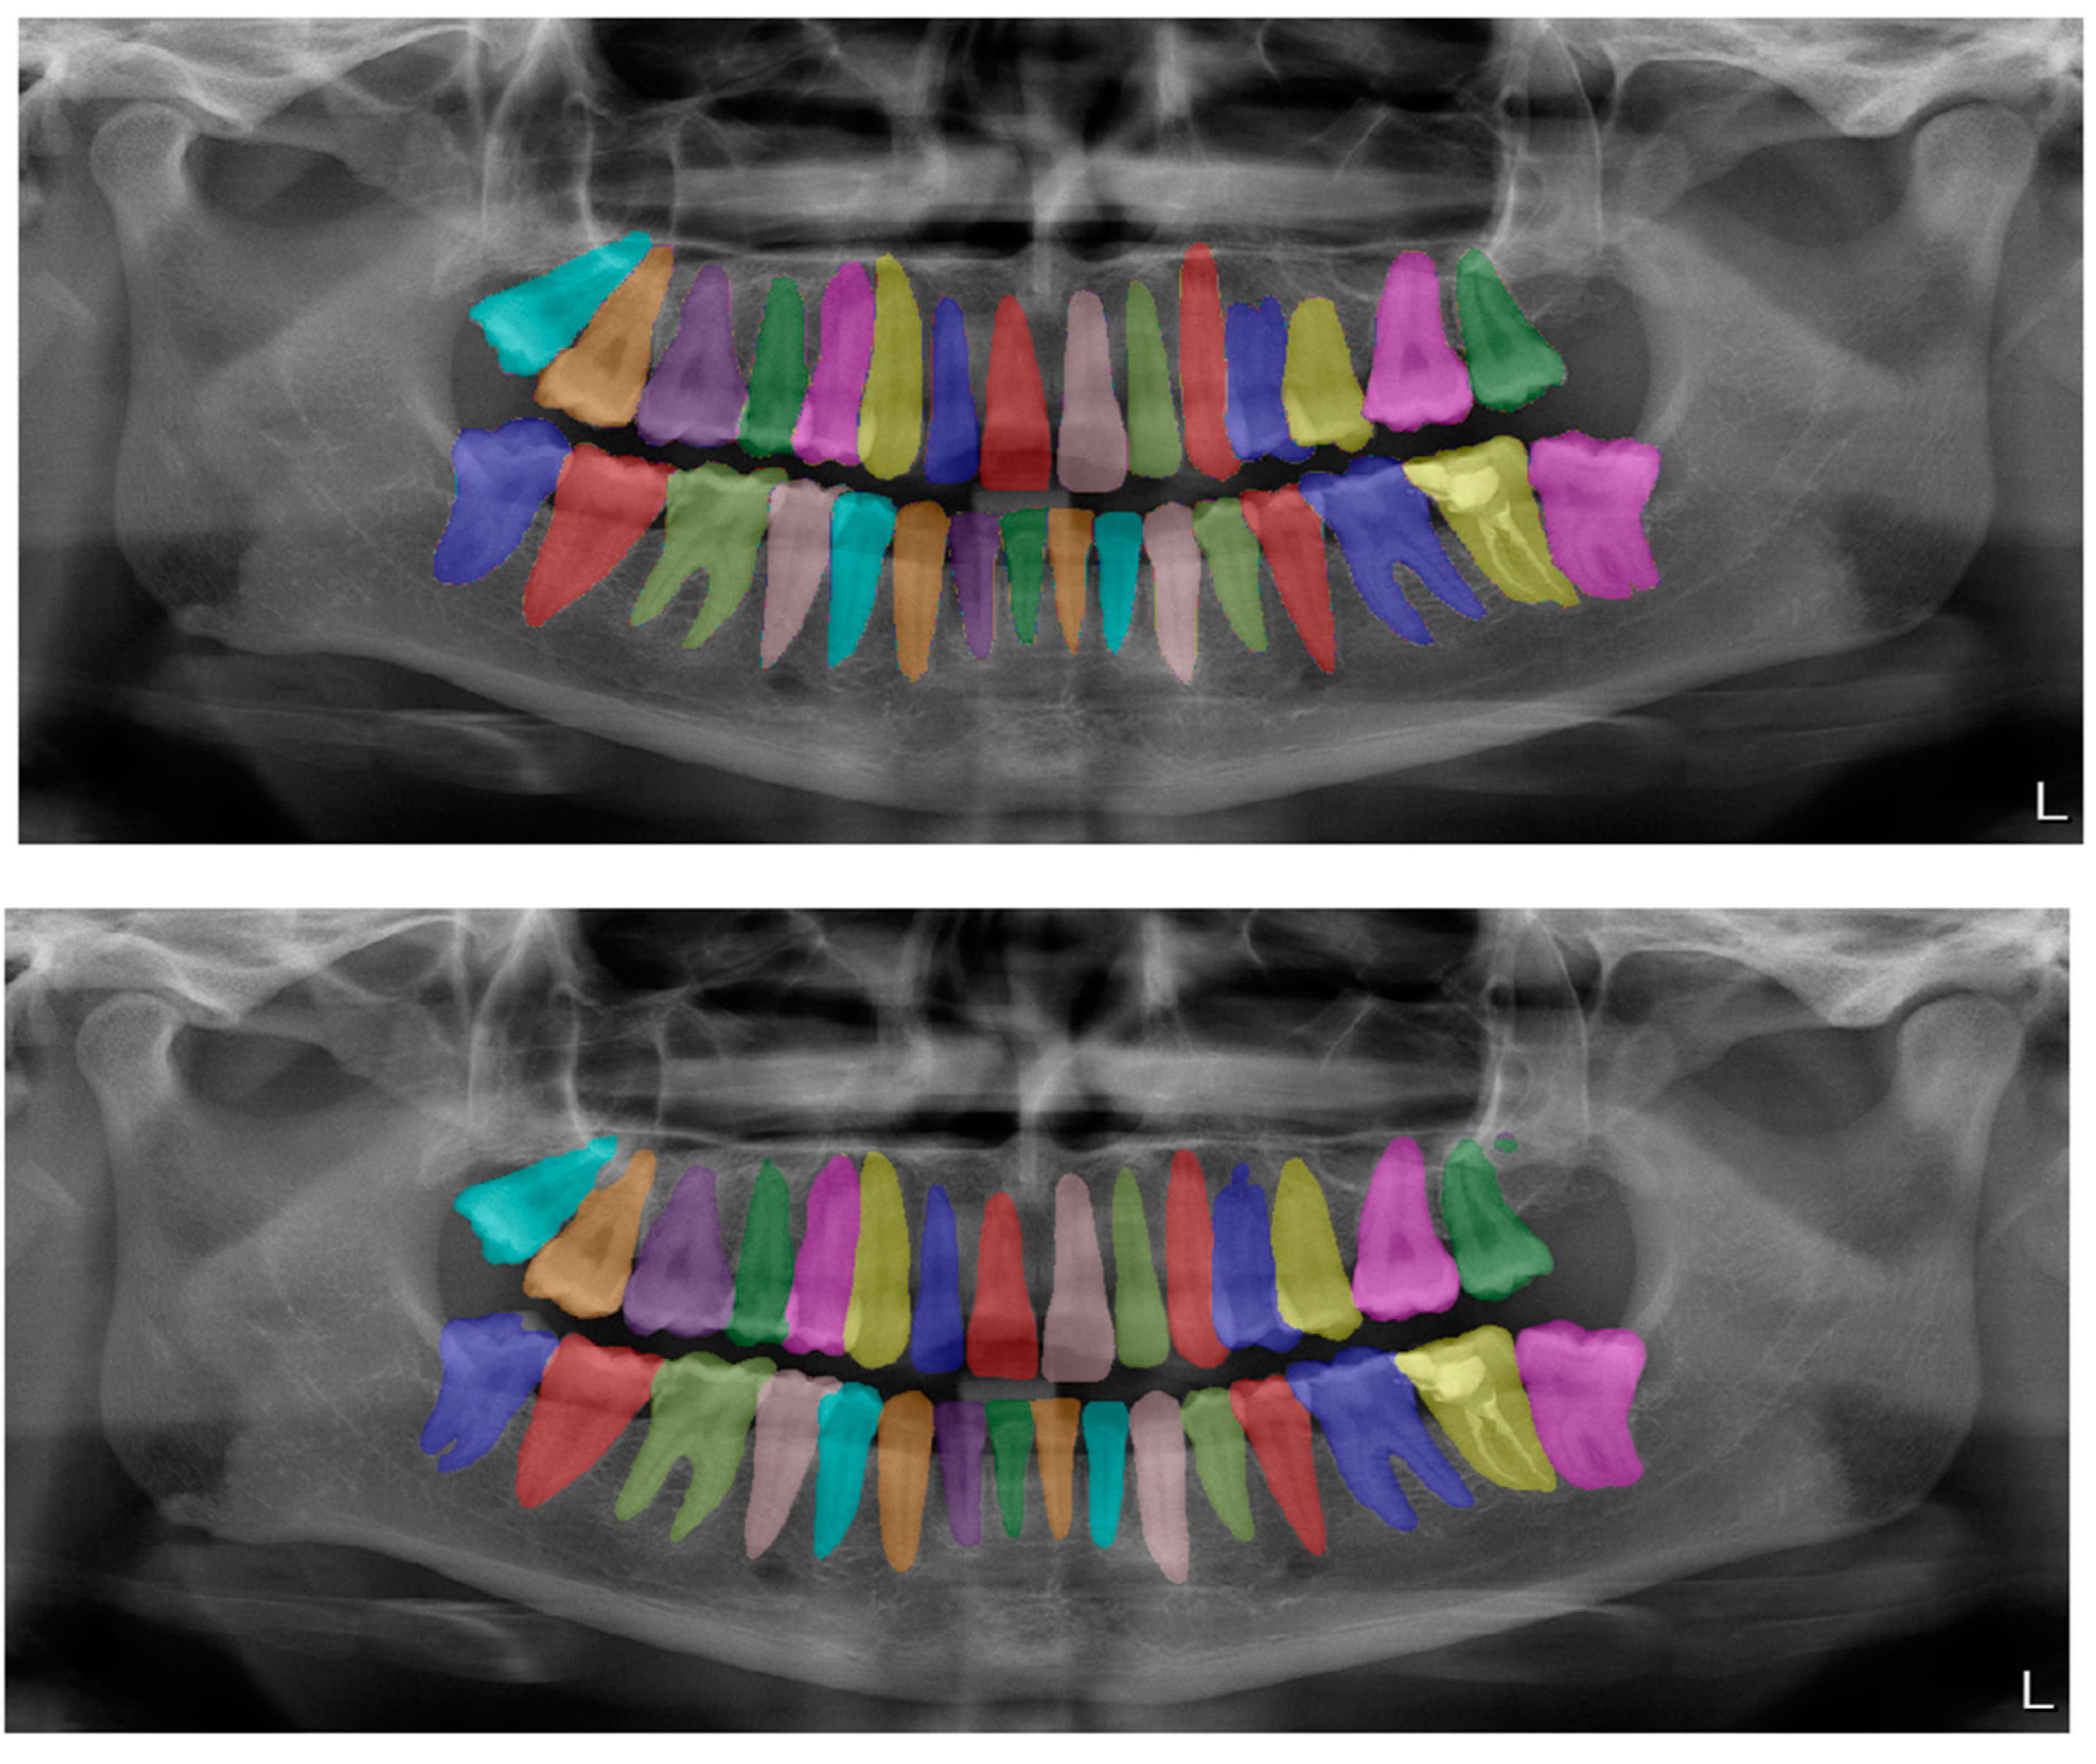

Figure 2.

Automatic segmentation of the teeth. Manual segmentation (upper image) and automatic segmentation (lower image) can be seen above. Each tooth has a unique label according to FDI World Dental Federation notation.